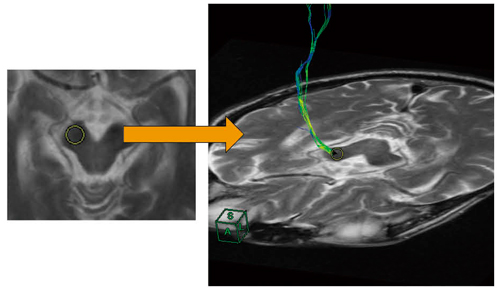

最後に,リアルタイムに局所的なDTI解析を行うことができる“インタラクティブファイバー”と呼ばれる機能について述べる。本機能では,図5に示すようにROIで囲んだ関心部位のDTIをリアルタイムで表示させることができるため,読影や手術中など,その場で必要とする神経線維についてオンデマンドにDTIが得られ,実用的なDTI解析機能として普及することが期待できる。

図5 インタラクティブファイバー表示

ファイバートラッキングさせたい部位にROIを置くと,リアルタイムにトラクトグラフィが作成される。